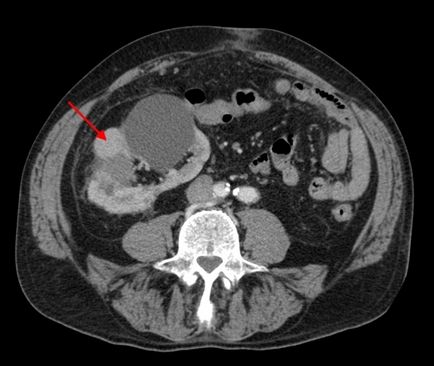

Parapelvikalnaya tumor

Parapelvikalnaya vese ciszta, egy fotó amely publikációkat a fenti hatással lehet nemcsak a bevonat réteg, hanem behatolnak a vesék, a test, ami miatt a beteg lehet diagnosztizálni többszörös szervi elégtelenség.

Fekete foltok képekben

A tumor a fejlesztési folyamatban képesek behatolni a mélyebb rétegek a veseszövet és provokál duzzanat és a kár a szomszédos szervekhez. Ez a folyamat látható a fekete pontok formájában az ultrahang képeket.

Növedékek vesék

Külső ciszták, amelyek a fedélhez csatlakoztatott veseszövet, lehet szkennelt ultrahanggal több szürke foltok szabálytalan alakú egyenes élek.